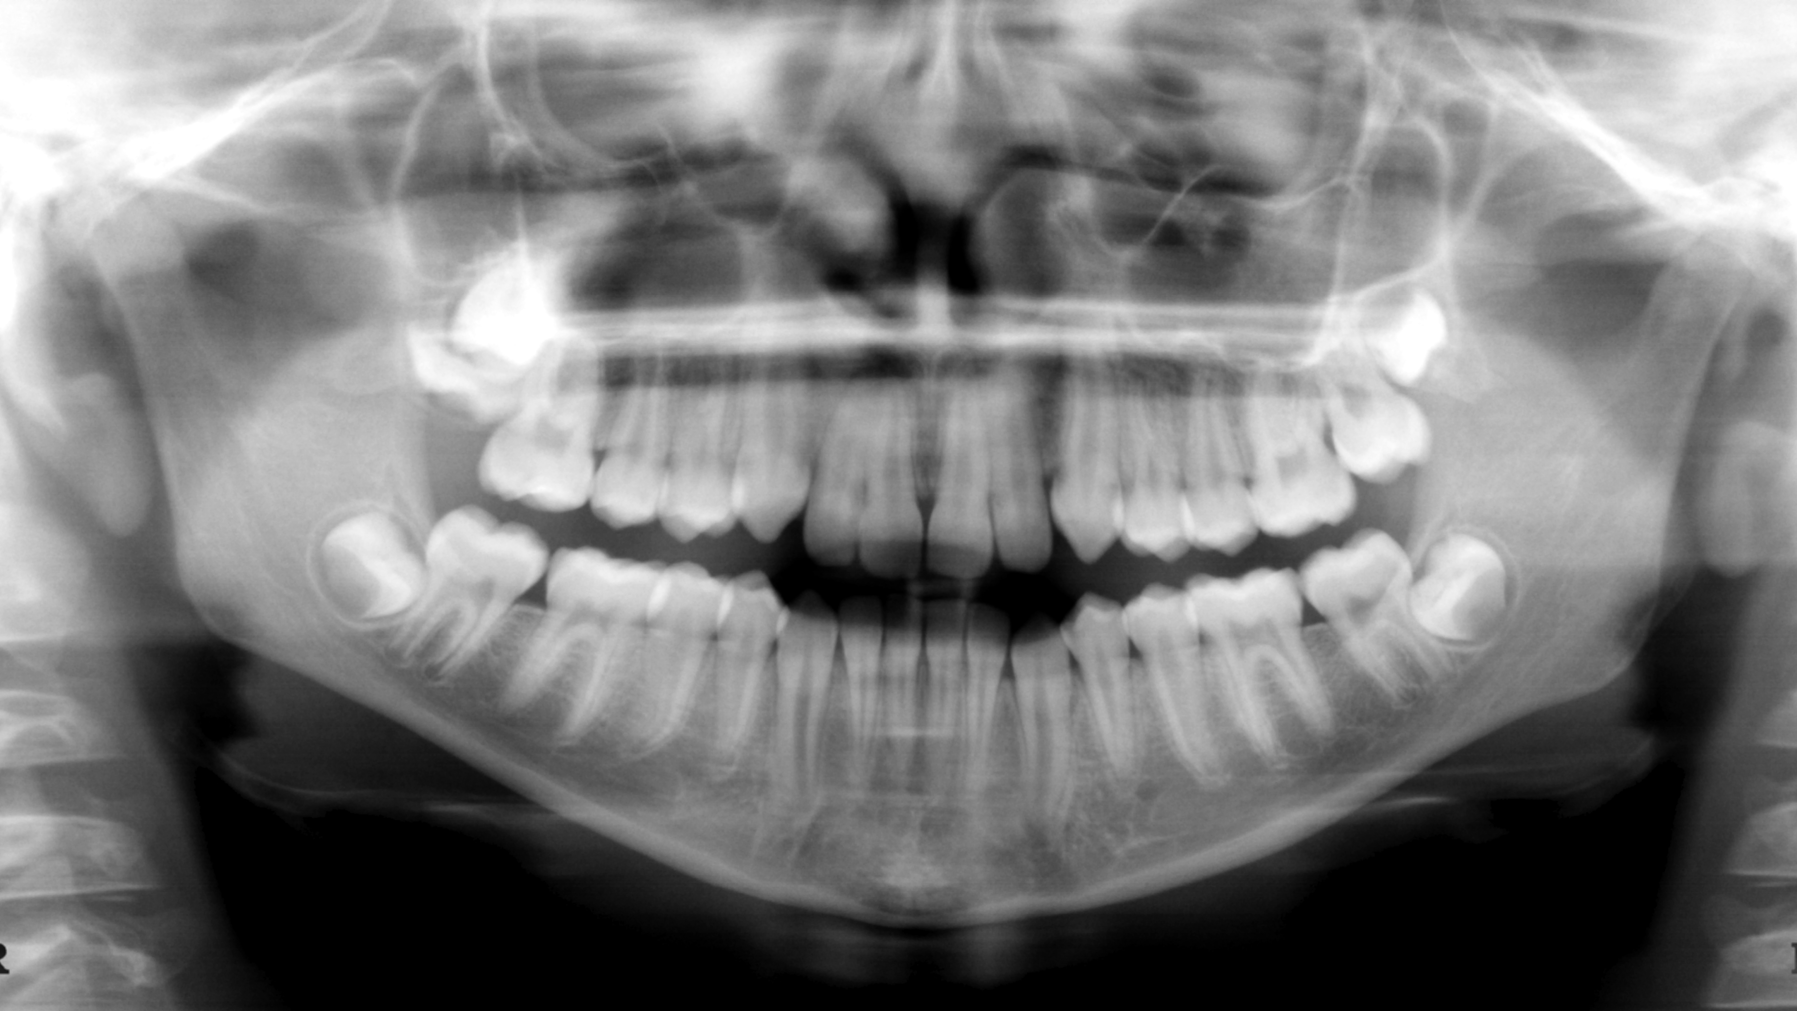

Private equity (PE) ownership can impact every facet of dentistry—from practice owners to staff to patients. What are its potential pros and cons?

A new study from Health Services Research coauthored by Health Policy Institute vice president Marko Vujicic reveals how PE can affect patient care, practice operations, finances, and more. Check out today's lead article for a breakdown of the data.